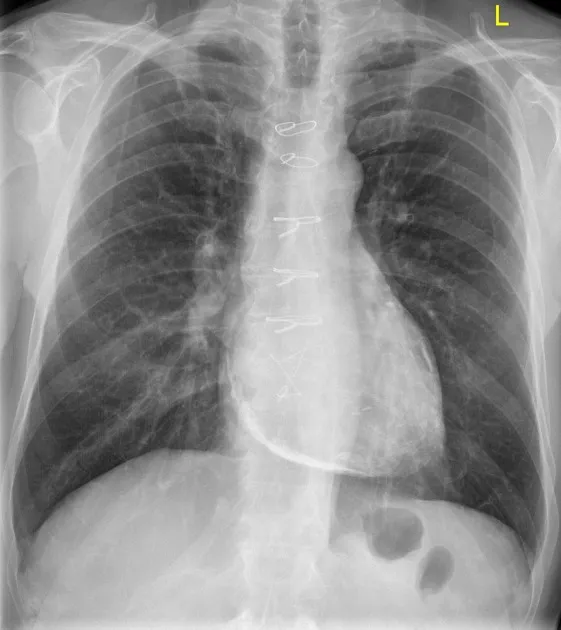

- CXR: Globular, "water-bottle" heart silhouette.